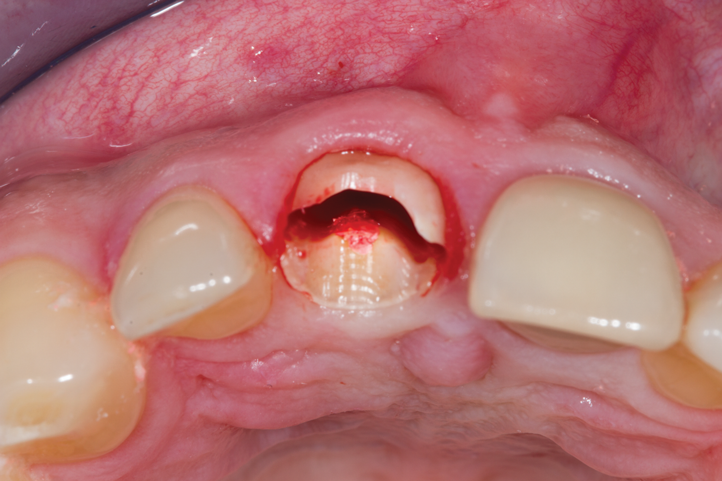

Fig 6. Initial preparation of the buccal aspect of the root to be retained.

Figure 6

Fig 7. Finalized preparation utilizing the PET protocol, with implant placement in the No. 8 (1:1) position. An “S”-shaped chamfer preparation was made internally to the retained buccal portion of the root.

Figure 7